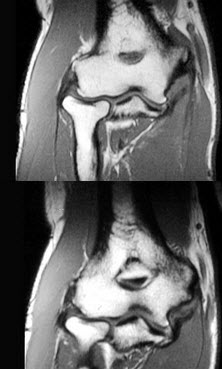

男,28岁,喜爱球类运动,内侧肘部疼痛3个月,结合图像,最可能的诊断是( )

A:尺侧韧带撕裂

B:未见异常

C:桡侧韧带撕裂

D:肱骨远端骨折

E:尺骨骨折